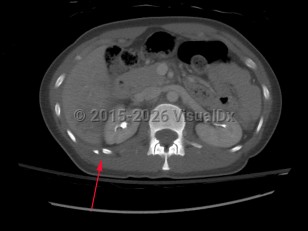

Causes / typical injury mechanism: Rib fractures are a common injury of the thoracic cage. They may be traumatic or pathologic. Depending on the location and the number of ribs involved, be alert for possible visceral injuries, pulmonary contusions, pneumothorax, or vascular injury.

Fractures of the lower ribs (9-12) could indicate concomitant intraabdominal injury.

Grade / classification system:

Rib fractures are commonly described as:

- Rib number(s), right or left

- Acute or chronic with evidence of healing from a remote incident

- Nondisplaced, > 2 mm displacement, comminuted, or flail chest

- Presence or absence of visceral injury